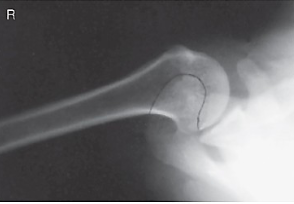

name the projection and rotational; label the part of the humerus the arrow is pointing to

AP external, greater tubercle